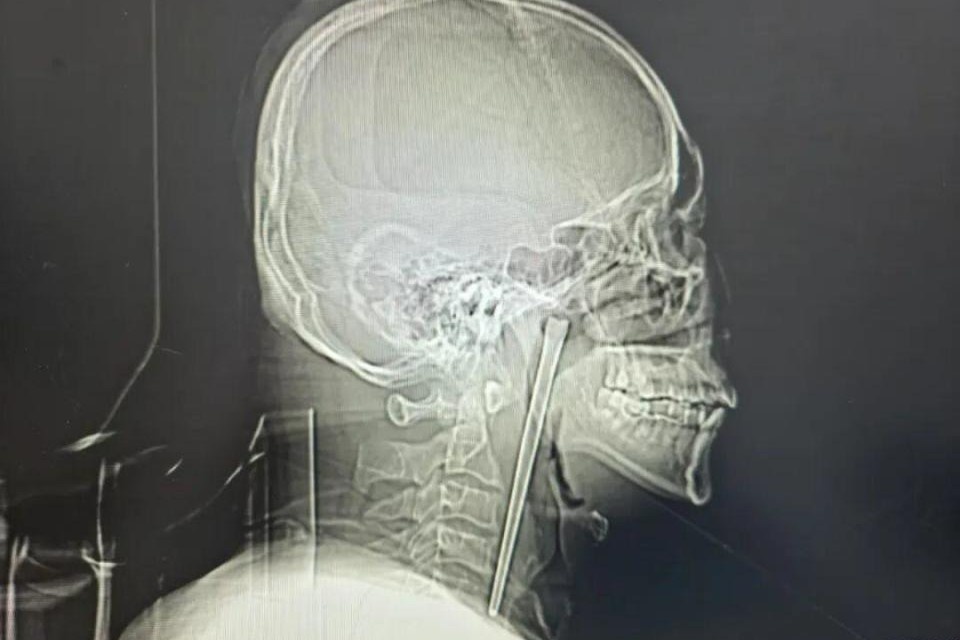

Chiếc đũa dài 12 cm mắc kẹt trong cổ họng người đàn ông suốt 8 năm

Người đàn ông 46 tuổi sống suốt 8 năm với chiếc đũa kim loại dài 12 cm mắc trong cổ họng. Ông chỉ đi viện khi cơn đau tăng dữ dội.

Dị vật là chiếc đũa inox trong cổ họng người đàn ông.

Kết quả kiểm tra khiến các bác sĩ bất ngờ, trong vùng họng của ông có một chiếc đũa kim loại dài khoảng 12 cm. Theo lời kể của bệnh nhân, sự việc bắt đầu từ 8 năm trước. Trong một lần ăn uống, ông vô tình nuốt phải cả chiếc đũa kim loại. Ngay sau đó, ông cảm thấy cổ họng nghẹn và đau, nhưng may mắn không bị khó thở.

Kết quả nội soi cho thấy một chiếc đũa kim loại cắm vào phần phía trên thành sau họng, nằm phía sau khẩu cái mềm bên phải. Phần đầu dị vật lộ ra khoảng 3 cm.

Do biết bệnh nhân từng từ chối phẫu thuật rạch cổ cách đây nhiều năm, các bác sĩ đã xây dựng phương án phẫu thuật ít xâm lấn hơn. Thay vì phải mổ ở cổ, ê-kíp quyết định thực hiện phẫu thuật lấy dị vật qua đường miệng. Cuối cùng, chiếc đũa kim loại dài 12 cm đã được lấy ra nguyên vẹn. Ca phẫu thuật diễn ra thuận lợi, lượng máu mất rất ít và không xảy ra biến chứng.